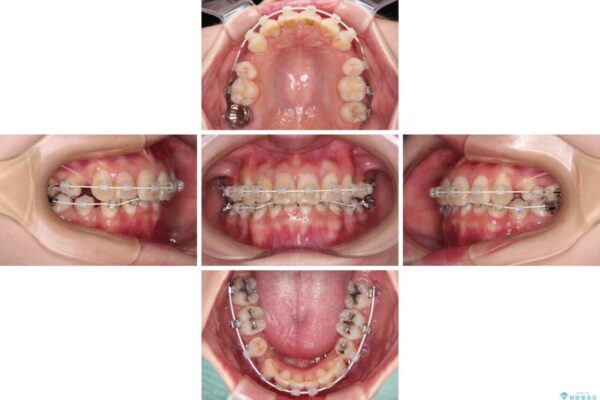

治療途中

• デコボコと深い咬み合わせ ワイヤー装置での抜歯矯正 治療途中画像